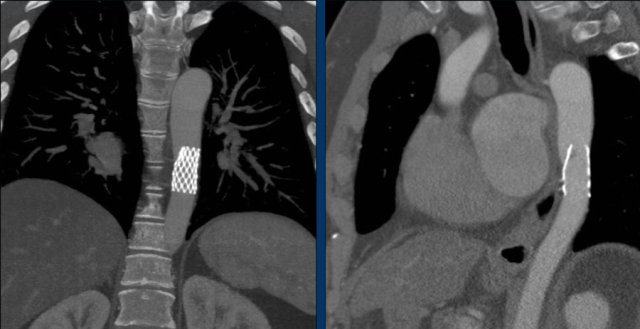

These are images of a patient with a persistent ductus arteriosus.

The ductus was closed with an Amplatz plug device.

Scimitar syndrome is characterized by partial anomalous pulmonary venous return, in which an abnormal right pulmonary vein drains into the inferior vena cava.

Correction is indicated in adults with signs of pulmonary volume overload or right heart dilation.

Scimitar vein pre- end post plugging.